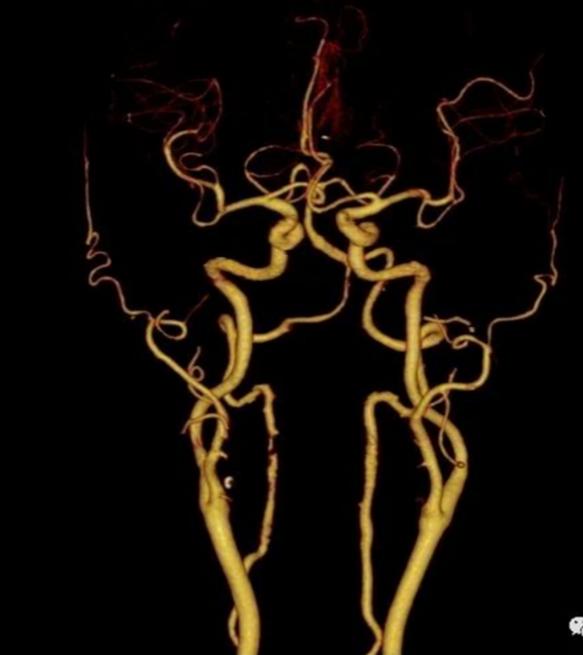

4小时余后就诊于当地医院,行头颅CT:左侧额叶及右侧颞叶脑梗死。头颅MRI:左侧颞叶、顶叶急性脑梗死,脑内散在缺血灶,左侧额颞叶及右侧脑室后脚旁软化灶,侧脑室周缘轻度白质脱髓鞘(图1)。头颅MRA:脑动脉硬化改变。

图1